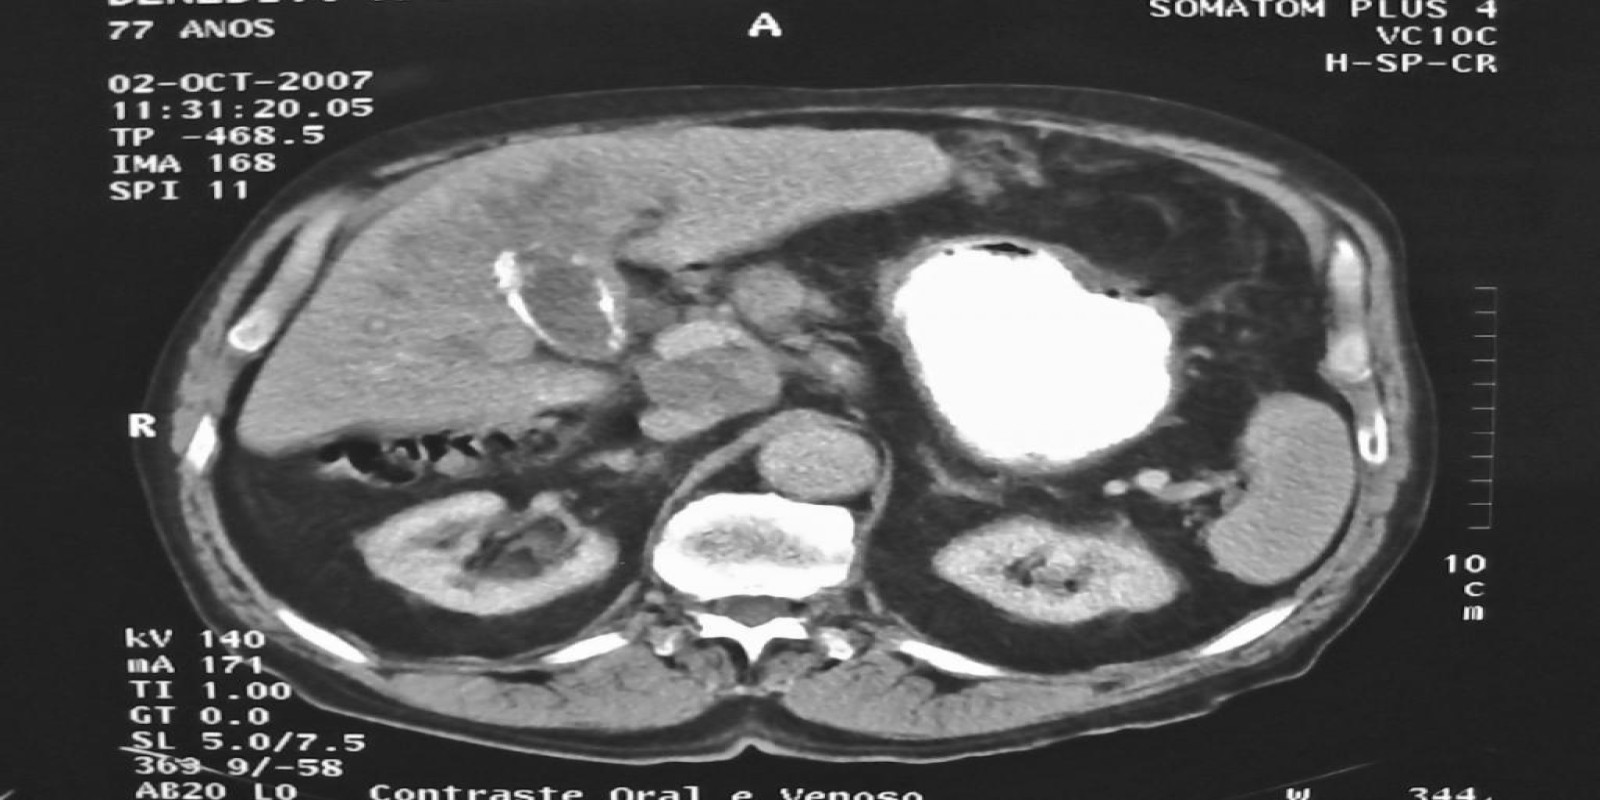

Caso Código 025D de Câncer da Vesícula Biliar

Cod.: 025D